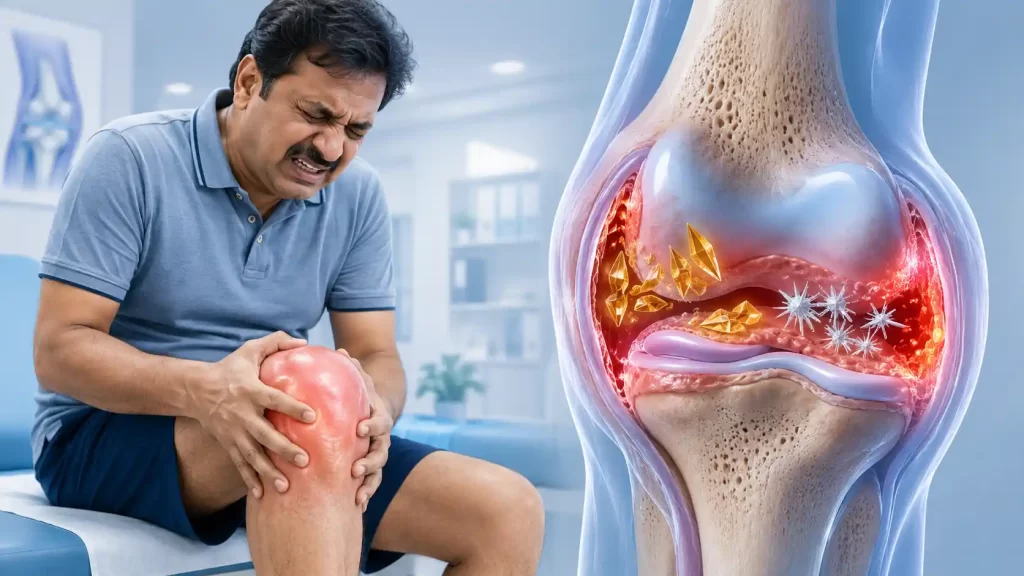

Gout is caused by deposition of monosodium urate crystals within the joint, triggering one of medicine’s most excruciating pain attacks. Though classically affecting the big toe, the knee is the second most common site — particularly in older patients and those on diuretics. Pseudogout involves calcium pyrophosphate crystals and tends to target the knee preferentially.

Both conditions cause sudden, intense inflammatory arthritis — the knee becomes swollen, hot, and exquisitely tender, often waking the patient from sleep. An acute gout attack in the knee can mimic septic arthritis and demands urgent assessment.

Acute attacks are managed with targeted anti-inflammatory measures. Long-term management focuses on urate-lowering therapy (co-ordinated with the patient’s physician) and joint protection. For patients with chronic tophaceous gout causing structural knee damage, our interventional toolkit — including ultrasound-guided joint aspiration and injection — provides rapid, effective relief.

Key Blood Test: Serum uric acid. Levels >6 mg/dL in women and >7 mg/dL in men suggest hyperuricaemia — but levels may be paradoxically normal during an acute attack. Joint fluid analysis (polarised microscopy) remains the gold standard.